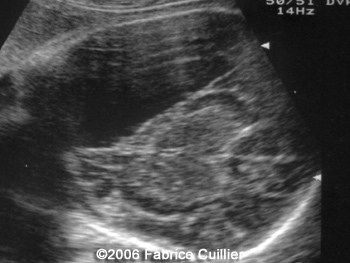

The following images are obtained in a 3rd trimester fetus:

The final diagnosis was: Arachnoid cyst